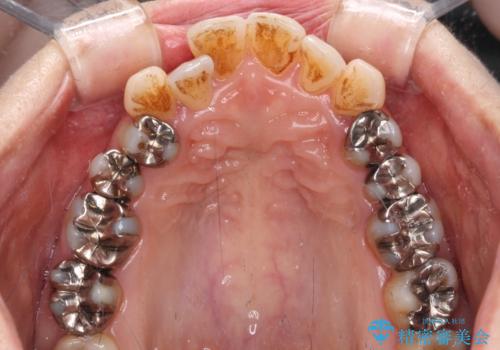

銀歯を白くしたい セラミックによる審美歯科治療

- 奥歯の銀歯をセラミックの白い歯にして、しみる症状も改善したいとのことで来院された患者様です。

知覚過敏の症状が強い歯と、銀歯の範囲や銀歯の下のむし歯が大きい歯は、インレー修復では対応が難しいためオールセラミッククラウンで、インレー修復で対応が可能な歯ではセラミックインレーにて修復することとしました。